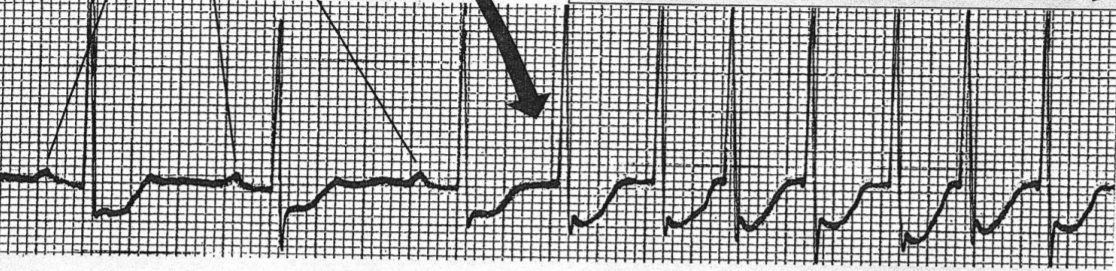

What is denoted by the Large arrow (P’)

Premature atrial beat

What is the shown pathology/arythmia

Paroxysmal Atrial Tachycardia